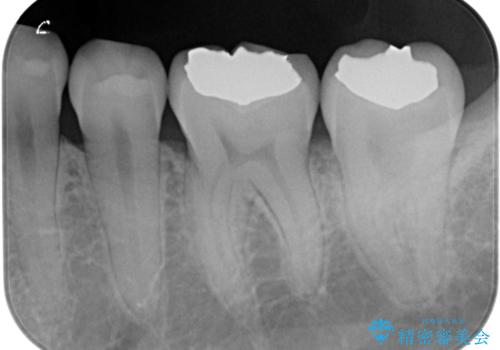

【歯に穴が空いている】ゴールドインレーで修復

セラミック、ゴールドの詰め物のご案内をしたところゴールドを希望されたのでゴールドインレーで治療を行いました。

- ゴールドインレー 9.9万円費用は治療当時の料金となります

ゴールドの詰め物は虫歯の再発のリスクが低い材料になります。